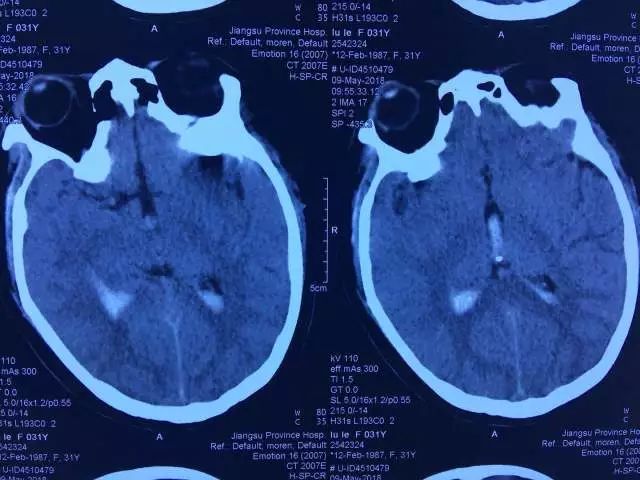

▲术前MR及CT

然而,好景不长,2017年3月,在山东潍坊出差的小鹿又一次出现了头晕头痛的脑出血症状,此后的2018年1月在徐州又发作了一次,小鹿只得前往上海跟着接受了立体定向射波刀治疗。没想到,不到半年的5月4日,小鹿在溧阳老家再一次发作了严重的脑出血!